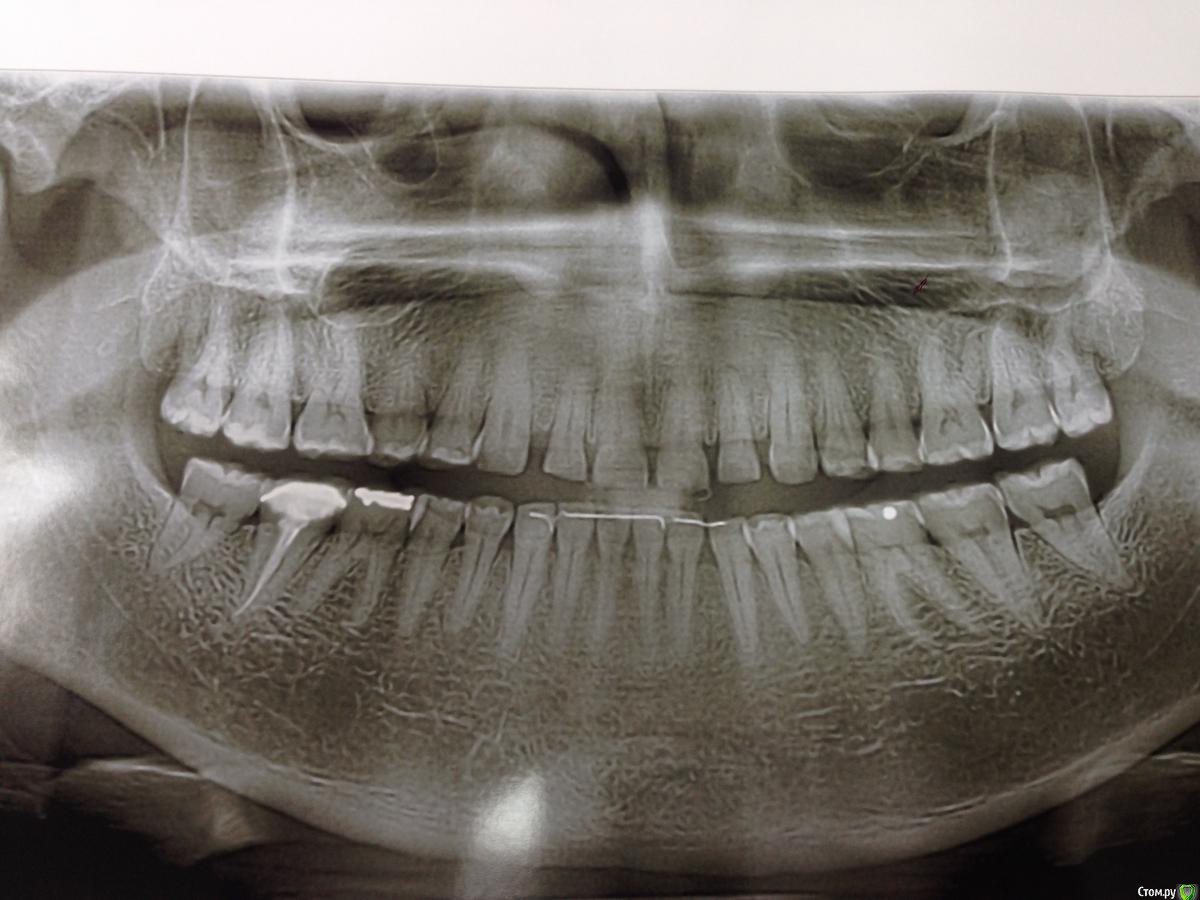

Supri Опубликовано 14 ноября, 2015 Поделиться Опубликовано 14 ноября, 2015 Уважаемые коллеги, подскажите пожалуйста план лечения для пациента с бруксизмом, повышенным стиранием и снижением высоты нижнего отдела лица. Хочет красиво и суперэстетично.Мой план таков: коронки из диоксида циркония до 4. С клыков E.max. Какие есть варианты? и можно ли поднимать прикус на вкладках керамических и винирах? Ссылка на комментарий

StomV Опубликовано 15 ноября, 2015 Поделиться Опубликовано 15 ноября, 2015 чем продиктован выбор до 4ок коронок на ДЦ,а остальное пресс?что есть "повышенное" стирание и как вы определили снижение высоты трети лица?Мое мнение,что прикус можно поднимать хоть на чем, главное что бы была окклюзионная формула верная, и направляющие.А так бы да,фото бы, и что с прикусом у пацинета? на панораме на нижних резцах ретенционная дуга? Ссылка на комментарий

Alexandr_doc Опубликовано 19 ноября, 2015 Поделиться Опубликовано 19 ноября, 2015 Если здесь бруксизм истинный, а не стираемость в результате проведенного ортодонтического лечения, то любое протезирование рискованно. Устранив причину стираемости можно любым материалом восстанавливать. А подымать прикус можно, на сколько зависит от конкретно данного пациента. Ссылка на комментарий